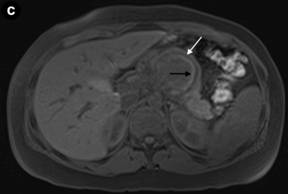

Figure 3. Axial fat-supressed (a.) and coronal (b.) T2-weighted MR images show a well-marginated lesion, heterogeneously hyperintense, in the body/tail of the pancreas, with a hypointense fibrous pseudocapsule. c. On an axial unenhanced fat-suppressed T1-weighted MR image the fibrous pseudocapsule is also hypointense (white arrow) and there is an internal peripheral high signal intensity rim (black arrow), a finding consistent with hemorrhage. |